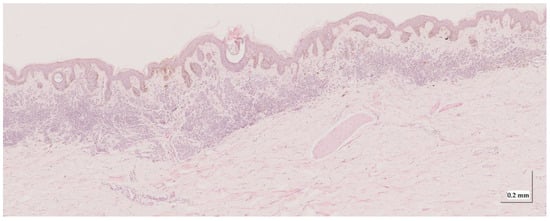

| Superficial spreading melanoma (SSM) Case 2 | Localization: right forefoot (right ankle) |

![]() | ![]() |